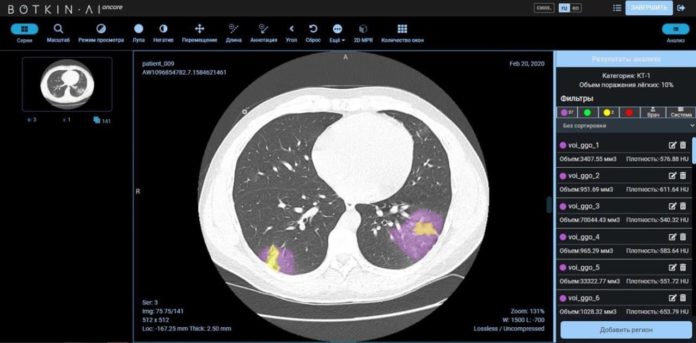

Продукт Botkin.AI измеряет процент поражения легких до десятых долей, что позволяет получать максимально объективные результаты исследования КТ, имеет широкую сферу применения и может быть использован при клинических испытаниях препаратов против коронавируса. Использование продукта Botkin.AI в исследовании позволит таргетно выделять пациентов, которым данная терапия будет наиболее эффективной.